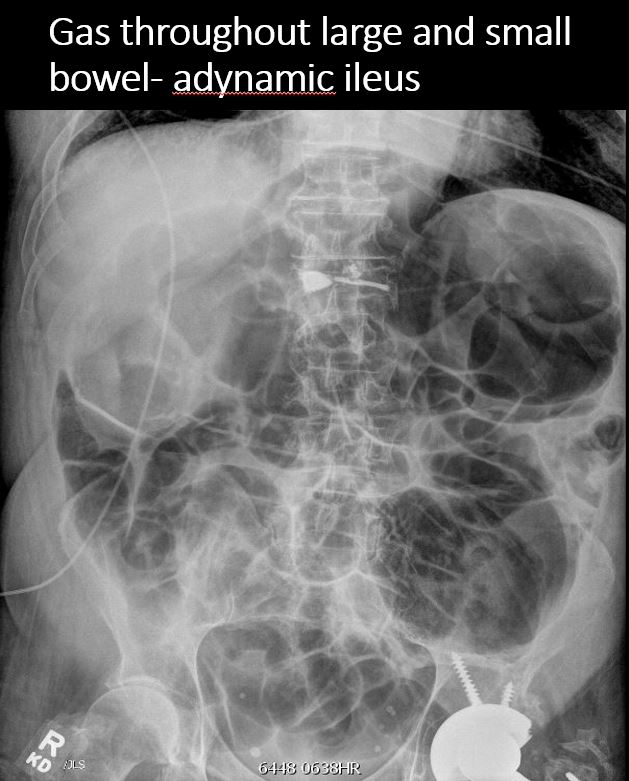

There is dilatation with gas or fluid of multiple or diffuse loops of bowel. [Yes/No]

​Both the small and large bowel are filled with air and/or fluid and may or may not be distended. [Yes/No]